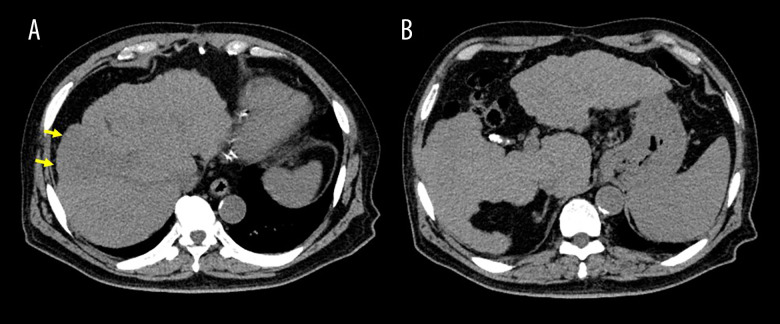

原发性肝神经内分泌肿瘤(PHNENs),包括原发性肝神经内分泌癌(PHNEC),是非常罕见的。尽管混合神经内分泌-非神经内分泌肿瘤预后较差,但PHNENs通常表现为生长缓慢。PHNENs的诊断也具有挑战性。病例报告一名73岁男性接受CT平扫时,偶然发现一个42毫米的孤立性肝脏肿瘤。缺乏维生素K或PIVKA-II诱导的血清蛋白水平升高至138 mAU/mL。13天后,磁共振成像(MRI)显示肝脏肿瘤扩大,肿瘤血栓延伸到肝静脉和门静脉。未观察到早期增强。第18天,多普勒超声和动态CT评估肿瘤为低血管,并出现新的肿胀的孤立淋巴结。第39天,正电子发射断层扫描(PET)/CT显示原发性肝脏肿瘤和转移性淋巴结强烈摄取,并出现其他远处淋巴结转移。第49天,手术切除转移性颈部淋巴结。在第61天,根据组织病理学和免疫组织化学评估明确诊断PHNEC。Ki-67标记指数为90%。在第67天,他住院开始化疗,但CT显示终末期疾病。需要姑息治疗,患者在最初诊断后82天死于癌症。结论:我们报告了一个令人深思的PHNEC病例,肿瘤进展迅速。为了阐明临床意义(例如,非典型影像特征和诊断缺陷),提供了详细的影像结果。我们期望这个病例将对该领域的临床医生提供信息。

BACKGROUND Primary hepatic neuroendocrine neoplasms (PHNENs), including primary hepatic neuroendocrine carcinoma (PHNEC), are extremely rare. PHNENs typically exhibit slow growth, although mixed neuroendocrine-non-neuroendocrine neoplasms have poor prognoses. PHNENs are also challenging to diagnose. CASE REPORT A 73-year-old man underwent plain computed tomography (CT), which incidentally detected a 42-mm solitary hepatic tumor. Serum levels of protein induced by vitamin K absence or antagonist-II (PIVKA-II) were elevated at 138 mAU/mL. Thirteen days later, magnetic resonance imaging (MRI) revealed an enlarged hepatic tumor with tumor thromboses extending into the hepatic and portal veins. No early-phase enhancement was observed. At 18 days, Doppler ultrasound and dynamic CT evaluated the tumor as hypovascular, and a newly swollen solitary lymph node appeared. At 39 days, positron emission tomography (PET)/CT revealed strong uptake in the primary liver tumor and metastatic lymph nodes, with additional distant lymph node metastases emerging. At 49 days, a metastatic cervical lymph node was surgically resected. At 61 days, PHNEC was definitively diagnosed based on histopathological and immunohistochemical assessments. The Ki-67 labeling index was >90%. At 67 days, he was hospitalized to begin chemotherapy, but CT revealed end-stage disease. Palliative treatment was required, and the patient died of cancer 82 days after the initial diagnosis. CONCLUSIONS We have presented a thought-provoking case of PHNEC with rapid oncological progression. To clarify clinical implications (eg, atypical imaging features and diagnostic pitfalls), detailed imaging findings are provided. We anticipate that this case will be informative for clinicians in this field.